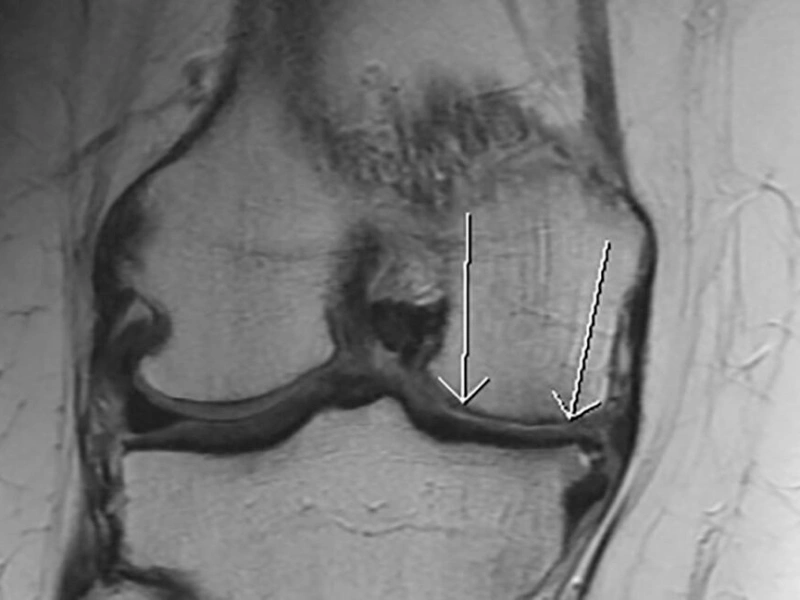

Otkrijte korisne informacije o magnetnoj rezonanci i njenoj ulozi u preciznoj dijagnostici bolesti i povreda zglobova.